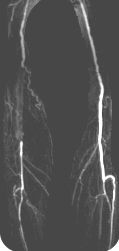

Contrast-Enhanced Subtraction MR Angiography (CE-MRA): State-of-the-art

CE-MRA of the aortic arch and

great vessels (top left) into the brain,

renal arteries (top), selective carotid

bifurcation (left) showing ICA/ECA

stenosis, and 3-section run-off

(right) showing multiple stenoses,

including long-segment bilateral

SFA stenoses.